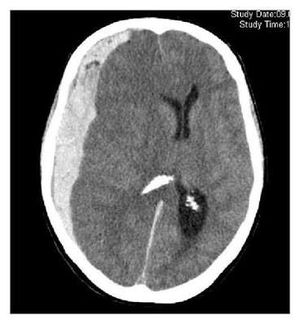

What’s your diagnosis???

Subdural hematoma with midline shift

Subdural hematoma ( acute )

SDH with midline shift